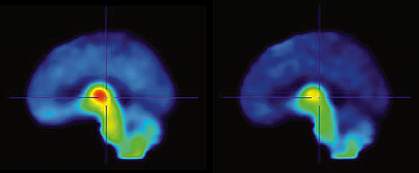

A team led by Dr. Arthur Brody of the University of California, Los Angeles, set out to study how secondhand smoke affects the human brain. They used an imaging technique to visualize when nicotine occupies brain nAChRs. The method depends on a special tracer molecule that binds specifically to nAChRs and can be detected by positron emission tomography (PET). Nicotine displaces the tracer molecule at the receptor, so the more nicotine that binds to nAChRs, the lower the tracer signals.

The researchers found that about 1 in 5 nAChRs in the brains of both smokers and non-smokers became occupied by nicotine after 1 hour of exposure to secondhand smoke. The smokers also had a significant increase in craving following exposure to secondhand smoke.